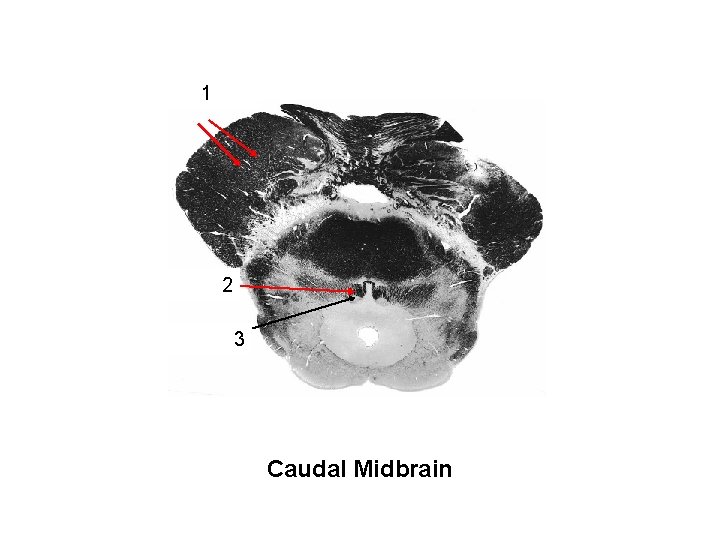

descending 1 fibers cortical 2 MLF Trochlear nucleus 3 Caudal Midbrain